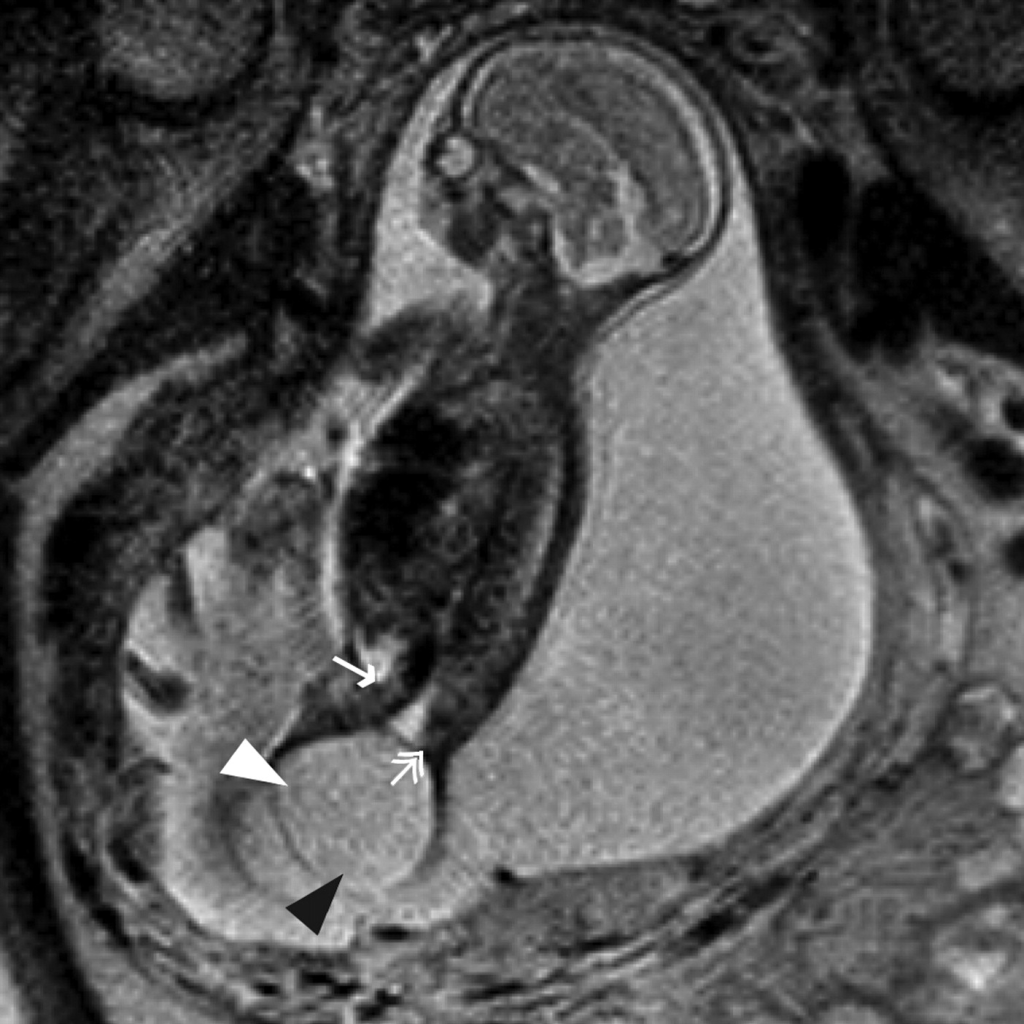

1-Teratom (özellikle Sakrokoksigeal Teratom)

- Dev, yüksek vaskülariteli

- Yüksek debili kalp yetmezliği

- Hidrops fetalis gelişimi

- Maternal ayna sendromu (mirror syndrome) riski